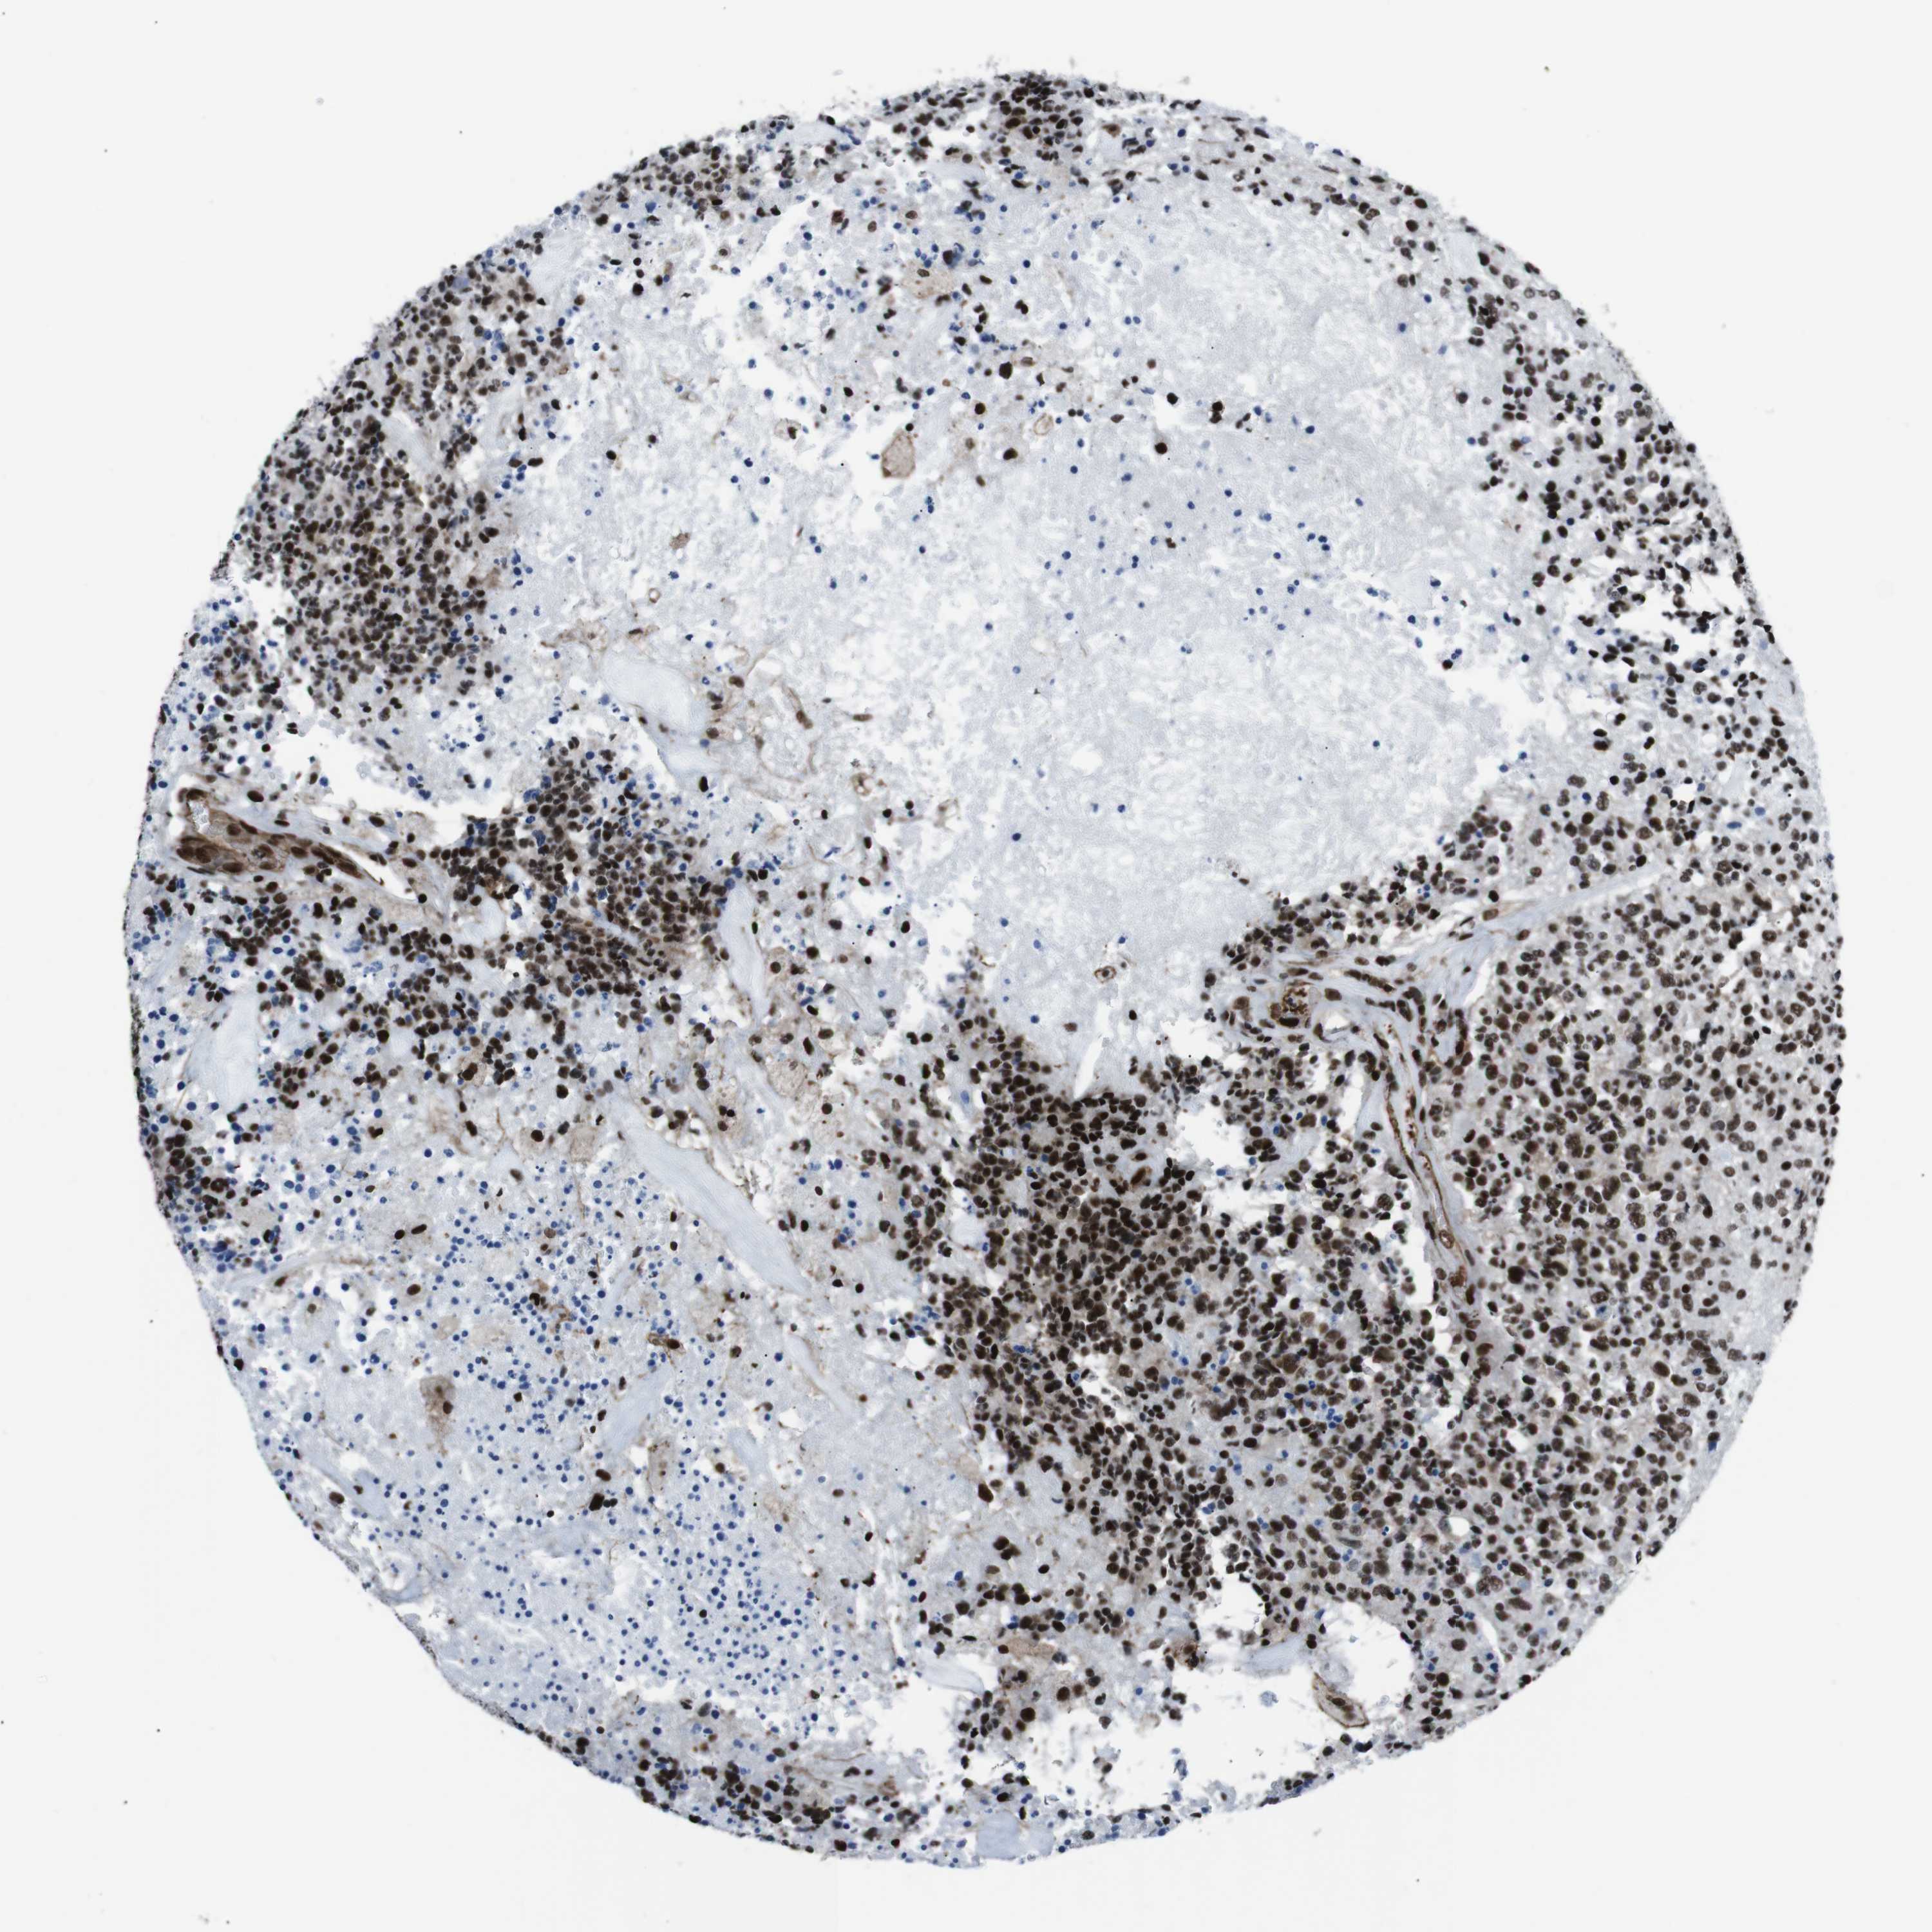

GLIOMA - Protein expressioni

A mouse-over function shows sample information and annotation data. Click on an image to view it in a full screen mode. Samples can be filtered based on level of antibody staining by selecting one or several of the following categories: high, medium, low and not detected. The assay and annotation is described here.

Note that samples used for immunohistochemistry by the Human Protein Atlas do not correspond to samples in the TCGA dataset.

Antibody stainingi

Antibody staining in the annotated cell types in the current human tissue is reported as not detected, low, medium, or high, based on conventional immunohistochemistry profiling in selected tissues. This score is based on the combination of the staining intensity and fraction of stained cells.

Each image is clickable and will lead to virtual microscopy that enables deeper exploration of all samples and also displays staining intensity scores, fraction scores and subcellular localization as well as patient and tissue information for each sample.

Antibody HPA041057

Antibody HPA058707

Antibody CAB011532

Staining

High

Medium

Low

Not detected

Intensity

Strong

Moderate

Weak

Negative

Quantity

>75%

75%-25%

<25%

None

Location

Nuclear

Cytoplasmic/membranous

Cytoplasmic/membranous,nuclear

Glioma, malignant, Low grade

Glioma, malignant, High grade